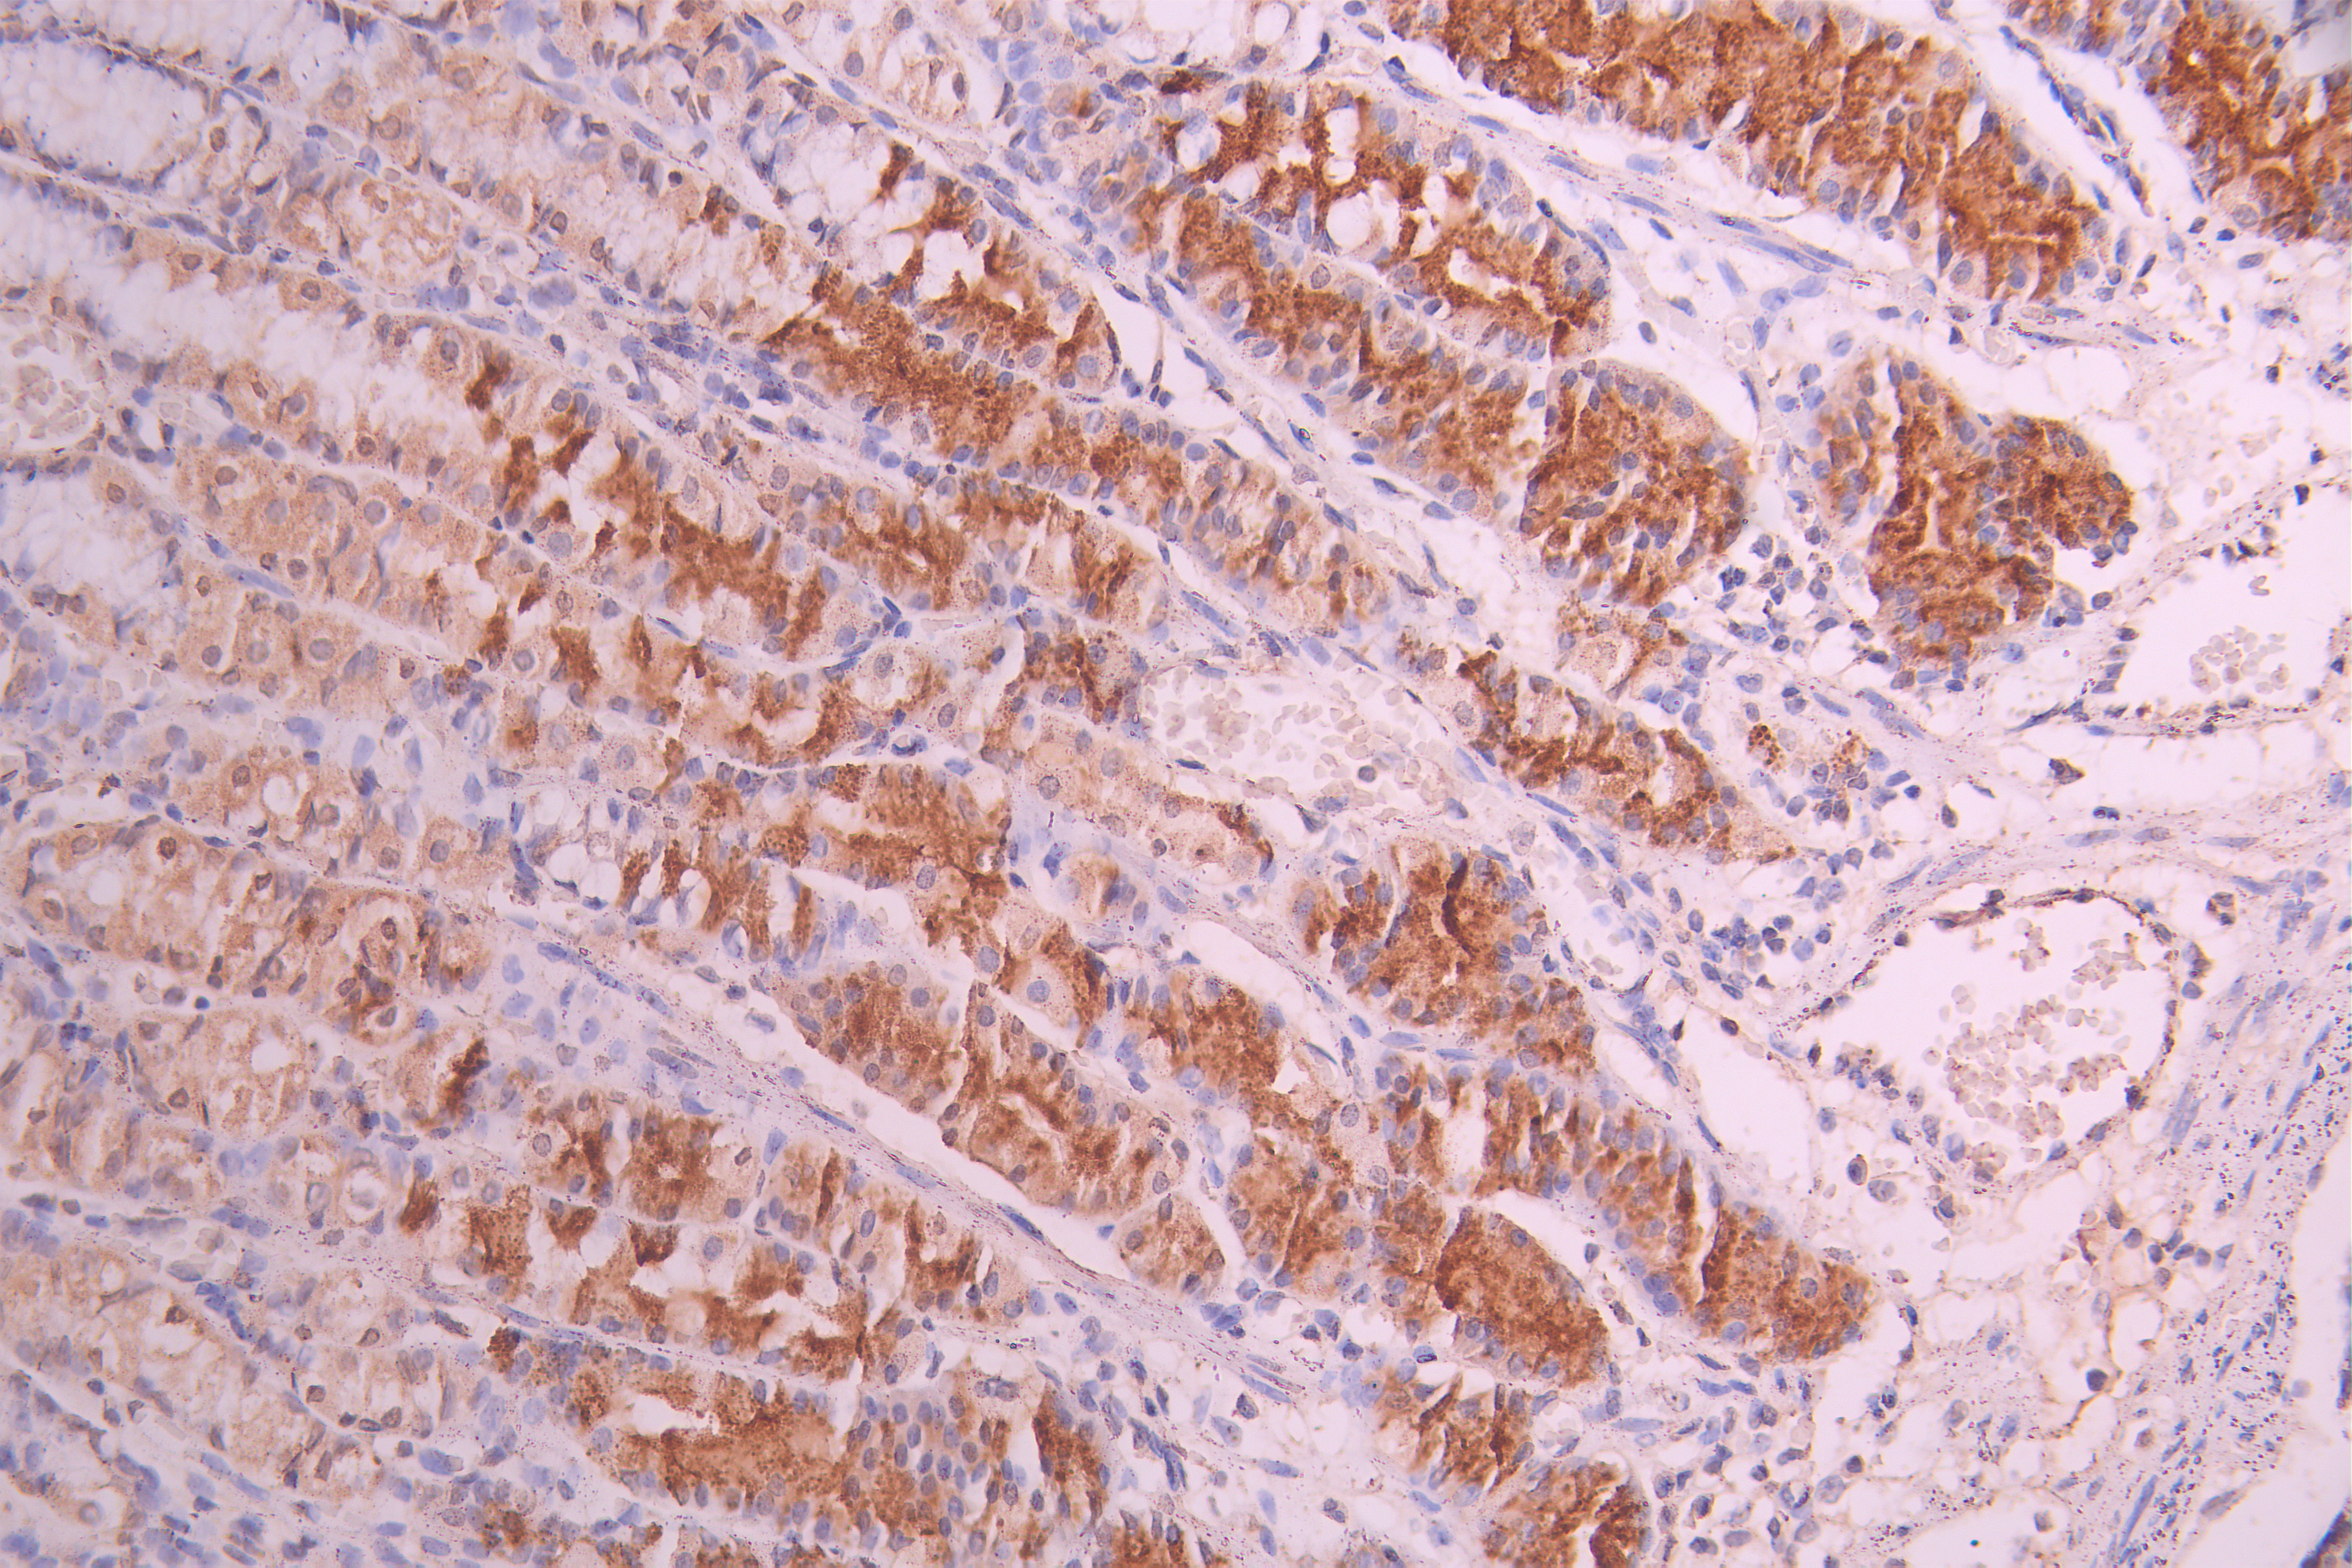

● PTH抗體